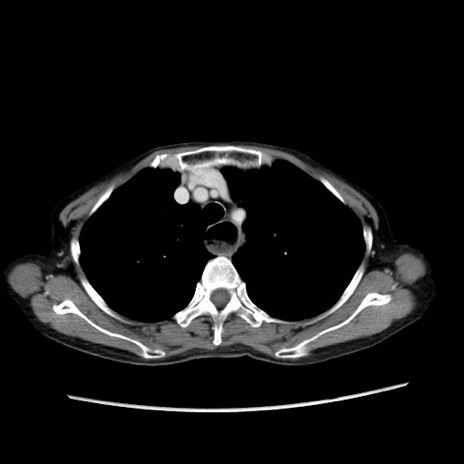

冠状断像